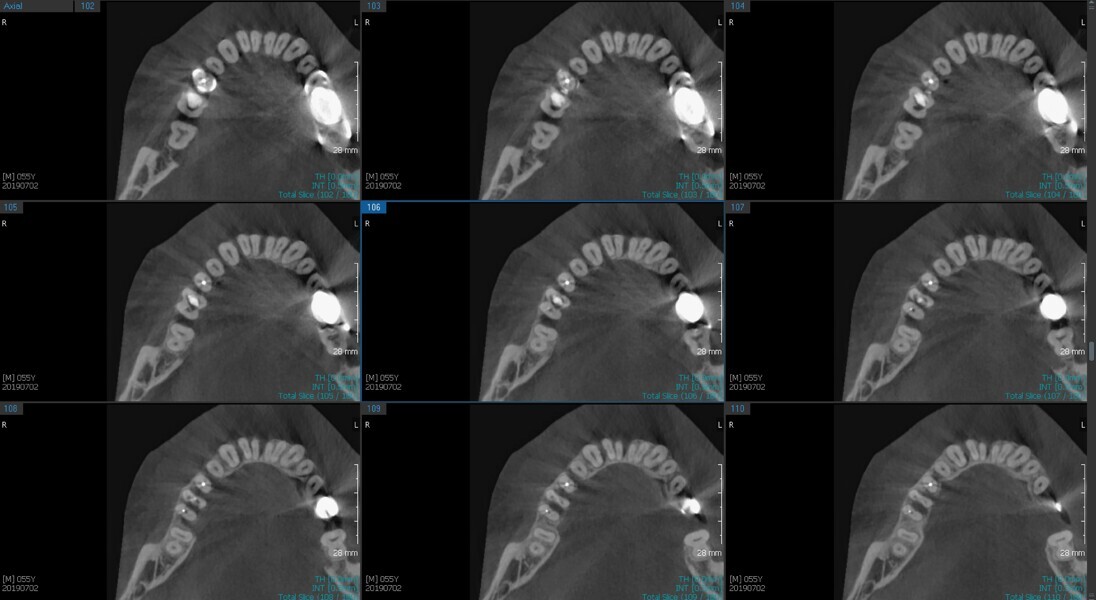

Fig. 6a: Post-op CBCT images of tooth #46 showing adequately obturated canals at all levels to the working length and sealing of the furcation defect.

Fig. 6b: Post-op CBCT images of tooth #46 showing adequately obturated canals at all levels to the working length and sealing of the furcation defect.

Fig. 6c: Post-op CBCT images of tooth #46 showing adequately obturated canals at all levels to the working length and sealing of the furcation defect.

Fig. 6d: Post-op CBCT images of tooth #46 showing adequately obturated canals at all levels to the working length and sealing of the furcation defect.

Fig. 6e: Post-op CBCT images of tooth #46 showing adequately obturated canals at all levels to the working length and sealing of the furcation defect.

Fig. 6f: Post-op CBCT images of tooth #46 showing adequately obturated canals at all levels to the working length and sealing of the furcation defect.

Fig. 6g: Post-op CBCT images of tooth #46 showing adequately obturated canals at all levels to the working length and sealing of the furcation defect.